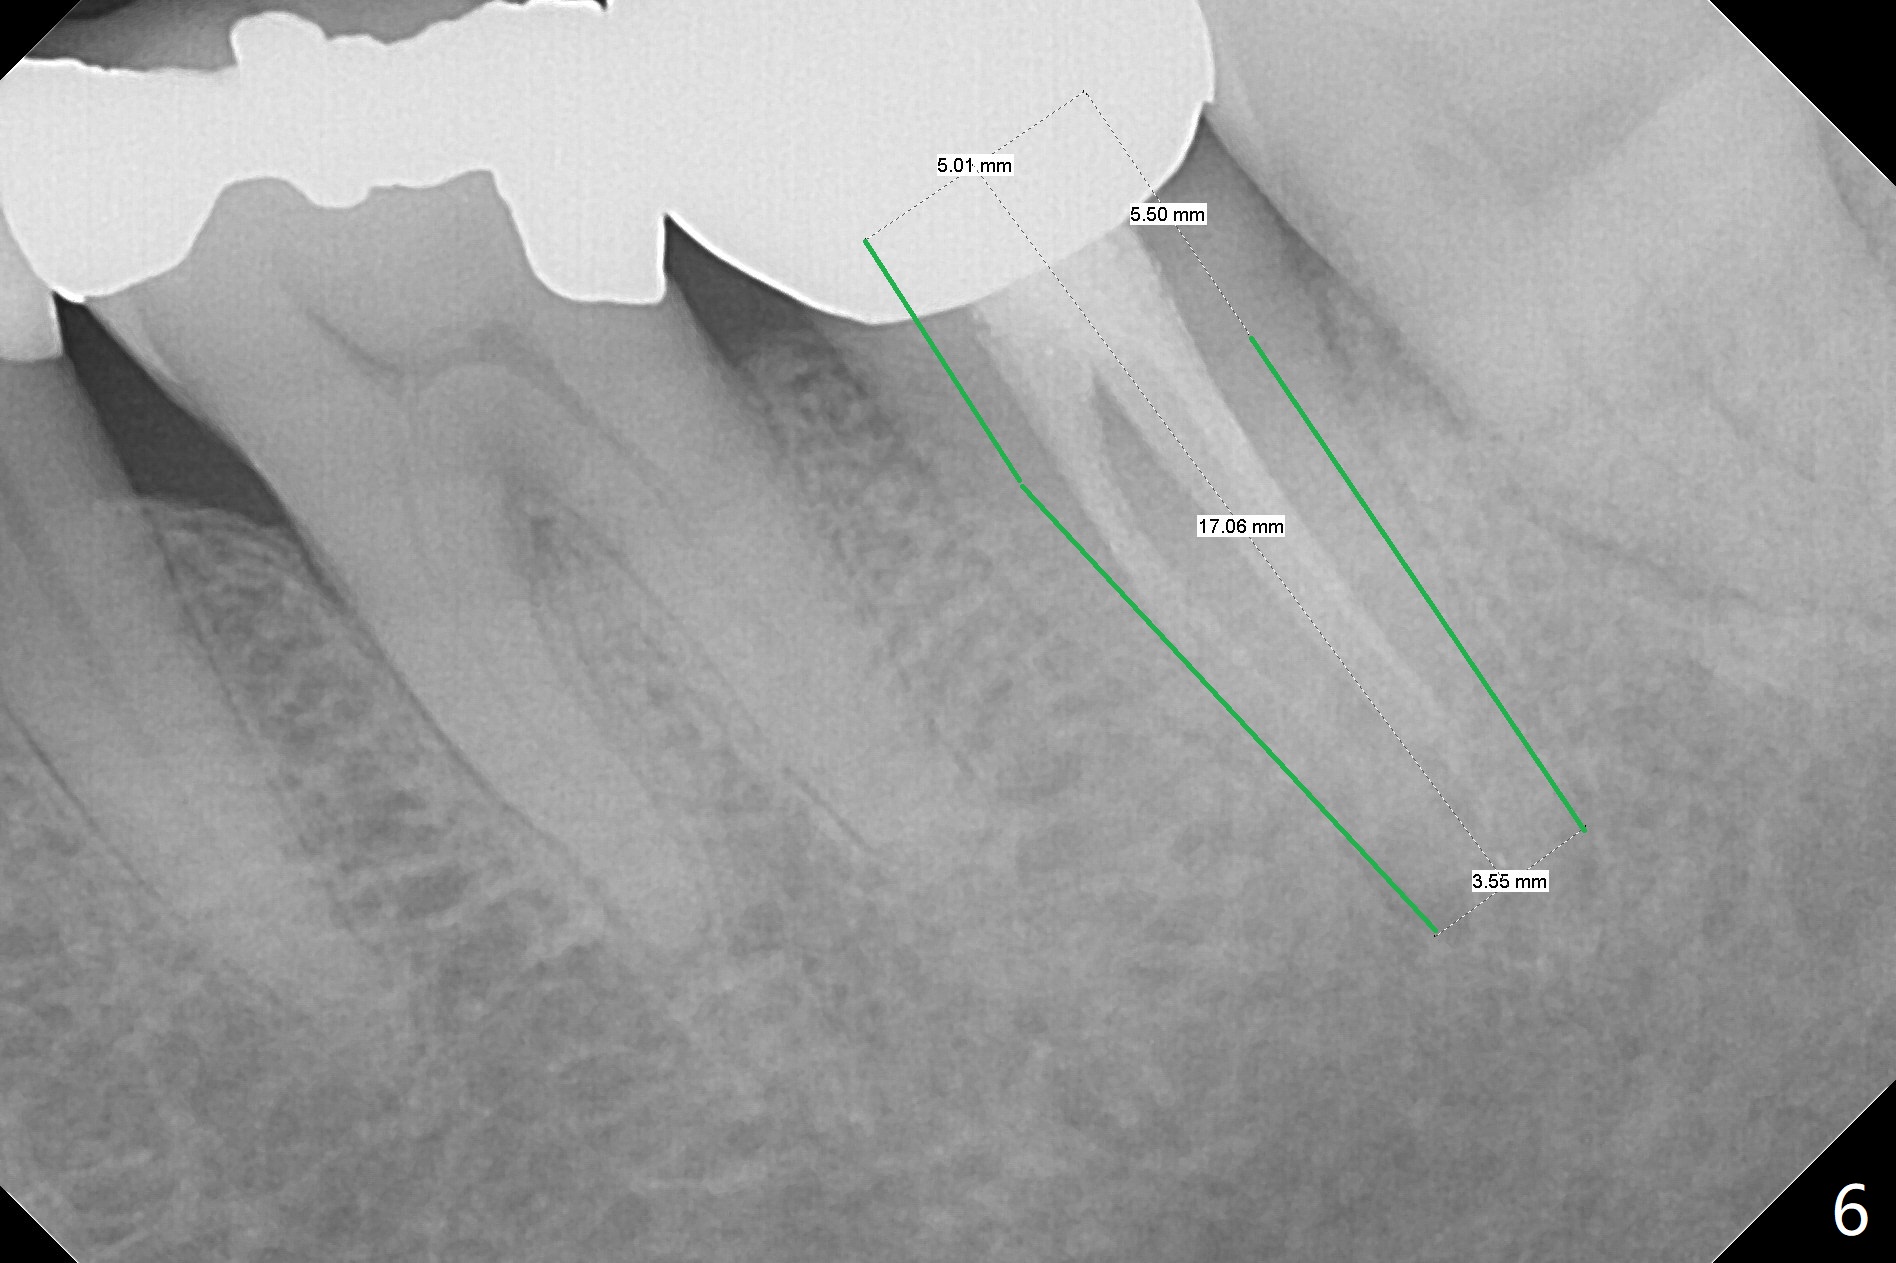

A 76-year-old man initially (3 years ago) presented to clinic for implant consultation 2 weeks after #2 extraction due to root canal failure. A 7x17 mm tissue-level implant was placed following bone expansion and tapping ~ 4 weeks post extraction. A 6x3 mm unipost was placed for immediate provi-sional. Impression was taken with retightening the unipost (no cementation) 3 months postop. Two weeks post cementation, the patient started to report food impaction at #18 crown (Fig.1). Eight months later, distal open margin was found; the tooth #3 seems to have occlusal trauma. Ten months later, #2 and 3 contact remains normal. Finally the crown at #18 was redone. ~1.5 years post cementation, #2 crown proximal contact becomes loose. The crown was redone with no occlusal contact. Retrospectively it is due to mesial shifting of the tooth #3. Nine months post cementation, the tooth #18 shows sign and symptom of root fracture (Fig.2). Antibiotic appears to alleviate the pain. Occlusal adjustment is done at #30 pontic to reduce trauma to #3 with symptom improvement (Fig.3).

In all, the patient should be a heavy bruxer. When extraction and immediate implant is done at #18, immediate provisional should be low and stable (keep bone graft in place). It appears that a temporary abutment can accomplish the purpose. An IS one has been trimmed. There are 2 options for implant placement: along the long axis of the socket (Fig.4 using taps for osteotomy) and in the mesial slope of the socket (Fig.5 using drills). If the bone level implant (tap) does not work, switch to tissue level one (Fig.6).